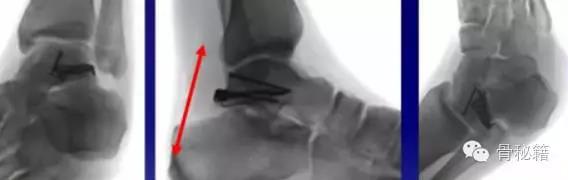

损伤主要位于以下几个主要部分体、颈、后突、外突

最主要的血供包括前方胫前动脉内侧胫后动脉外侧腓动脉的分支(跗骨窦)

当发生骨折脱位时,由于位移巨大,导致相应位移的血管损伤、最终导致距骨坏死所以距骨骨折的分型常用Hawkins分型距骨坏死率随分型严重程度逐渐增加